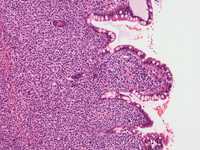

Biopsy findings in MCL case

Trephine biopsy is hypercellular (approximately 95% cellularity). Focal areas of infiltration with mostly round multinucleated and some spindle-shaped mast cells are present. A slight increase in lymphocytes and eosinophils in the areas of infiltration are noted. Large multinucleated forms should not be confused with megakaryocytes.